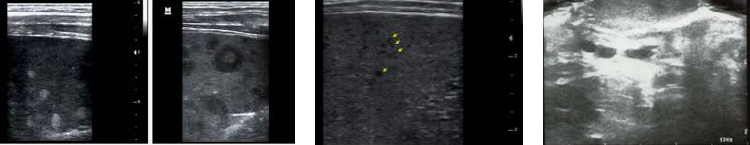

hepatic candidiasis

(most commonly) pneumocystis carinii (associated with hepatic granuloma)

hepatic granulomas (associated with pneumocystis carinii)